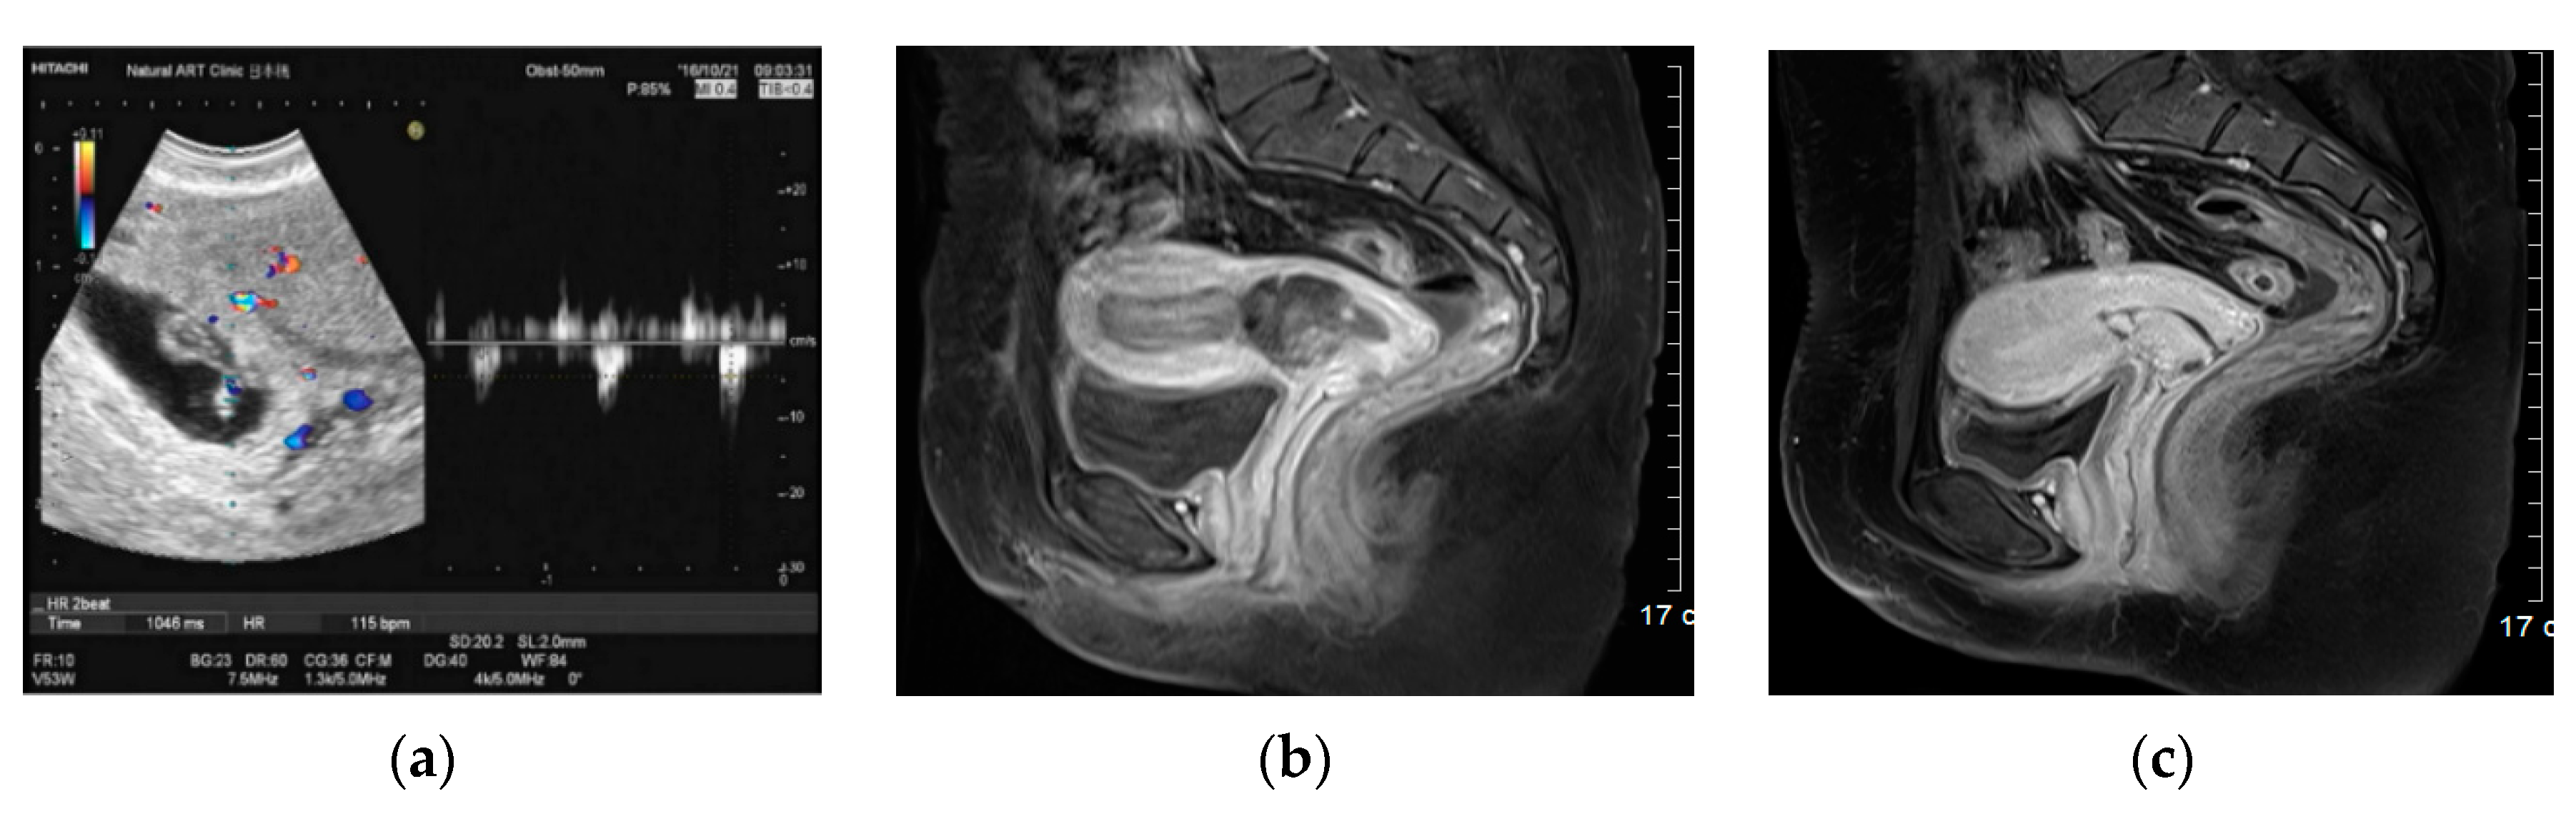

Figure 2. Transvaginal ultrasound Doppler image and pelvic MRI scan of cesarean section scar pregnancy with positive fetal heartbeat. (a) Transvaginal ultrasound Doppler image demonstrating FHB-positive CSSP. (b) Axial sections of pelvic MRI before the injection; initial serum β-hCG level was 43,596 mIU/mL and that at 2 h after the AE injection was 32,161 mIU/mL, demonstrating a reduction rate of 26.2%. (c) Axial sections of pelvic MRI on day 25 of the injection. Serum β-hCG level was 6.8 mIU/mL (on day 38, the level decreased to < 1.0 mIU/mL).